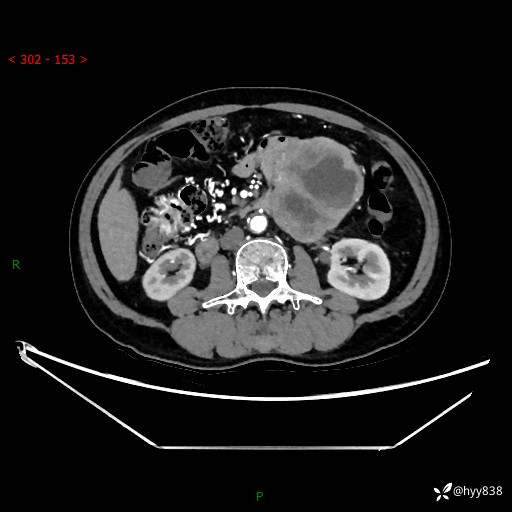

年龄:61岁

主诉:发现腹膜后肿瘤3天

腹部CT平扫+增强(动脉期+静脉期)